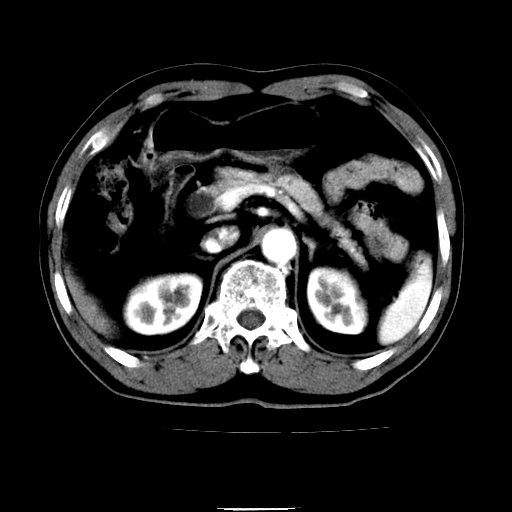

以下是引用chenqiong在2010-3-25 20:56:00的发言:[br]1、胆囊炎,胆囊息肉[br]2、肝内胆管及胆总管扩张,胆总管下端结石[br]3、十二指肠乳头旁憩室

以下是引用zxl51642在2010-3-26 10:47:00的发言:[br]胆囊炎,胆囊息肉,胆总管扩张,但未看到明显肿块,肝内胆管扩张不像恶性,炎性狭窄或阴性结石可能吧,建议mrcp,右肾小囊肿